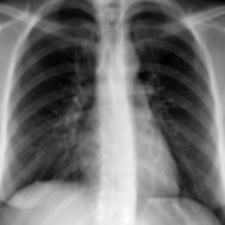

Tuberculosis remains a critical global health issue, particularly in resource-limited and remote areas. Early detection is vital for treatment, yet the lack of skilled radiologists underscores the need for artificial intelligence (AI)-driven screening tools. Developing reliable AI models is challenging due to the necessity for large, high-quality datasets, which are costly to obtain. To tackle this, we propose a teacher--student framework which enhances both disease and symptom detection on chest X-rays by integrating two supervised heads and a self-supervised head. Our model achieves an accuracy of 98.85% for distinguishing between COVID-19, tuberculosis, and normal cases, and a macro-F1 score of 90.09% for multilabel symptom detection, significantly outperforming baselines. The explainability assessments also show the model bases its predictions on relevant anatomical features, demonstrating promise for deployment in clinical screening and triage settings.